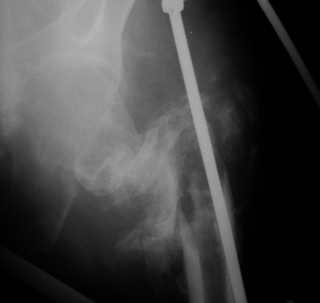

Вот снимки по свежей ситуации, парень 19 лет, длинный оскольчатый перелом бедра от шейки до в-с/3. давно уже ходит на своих ногах.

Dear Евгений.

Представленные Вами рентгенограммы действительно являются примером качественной фиксации спице-стержневым аппаратом. Они, как ни что другое, многое иллюстрируют.

Кроме того, было бы ошибкой ставить знак равенства между нашим и Вашим пациентами. Они не только не похожи, разница между ними просто огромная. Говорю это не для того, чтобы задеть Вас или обидеть. Ни в коем случае. Просто теперь я понимаю, что Ваше мнением строится на простом преломлении Ваших подходов к лечению пациентов со свежими переломами, на ситуацию, абсолютно несопоставимую, подобную нашей.